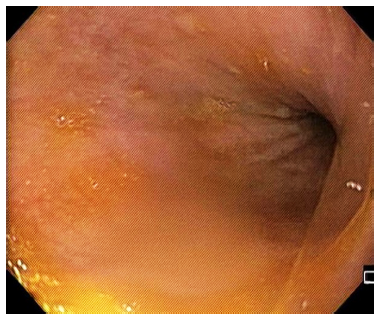

Dados los hallazgos encontrados en las imágenes diagnósticas, así como la edad avanzada de la paciente y las comorbilidades que confieren alto riesgo quirúrgico, se decide realizar abordaje endoscópico mediante el que se logra devolvulación gástrica endoscópica, sin complicaciones (Figura 3).